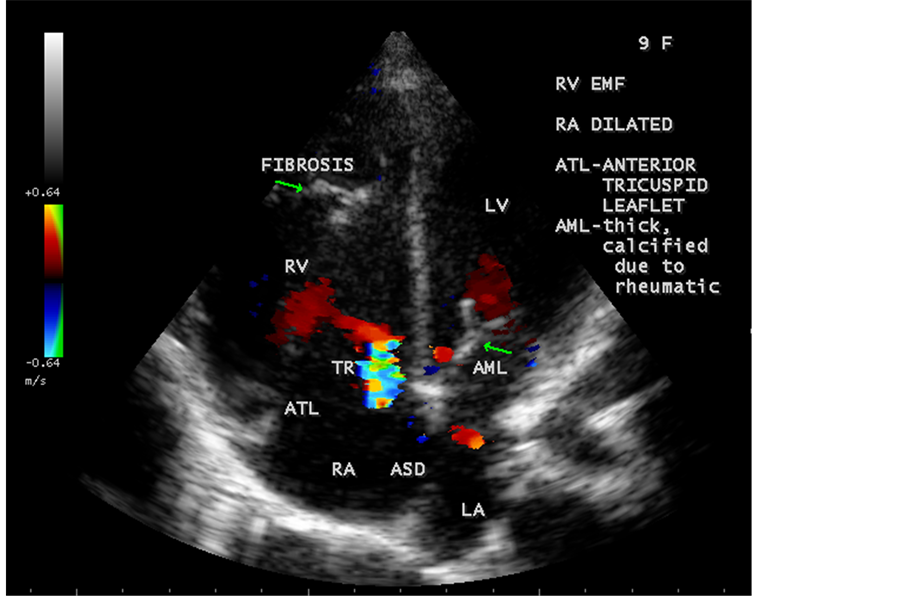

Figure 64. RV EMF associated with ostium secundum atrial septal defect with rheumatic mitral valve involvement in a 9-year-old female with positive serum ASO titer (anti-streptolysin O).

Figure 65. RV EMF with ASD (atrial septal defect) in a 9-year-old female.

Figure 66. RV EMF with ASD-mimic Ebstein’s anomaly in a 9-year-old female (apical fibrosis extending to tricuspid valve and the valve is tethered with fibrosis and mimic Ebstein’s malformation of the tricuspid valve and the right ventricle (RV) is dilated due to left to right shunt).

ventricle”) in a 16-year-old female as shown in Figure 50 to Figure 53 were detected. RV EMF with rheumatic involvement of mitral valve as shown in Figure 54 and Figure 55 in a 44-year-old female and in Figure 63 in a 55-year old female. Biatrial enlargement due to rheumatic atrioventricular (AV) valves (mitral and tricuspid) involvement characterized by stenosis of the valves are illustrated in Figure 56 to Figure 59 in a 54-year-old female and it is differentiated from EMF which is characterized by AV valve regurgitation as shown in Figure 34 and Figure 60. RV EMF associated with thickening and fibrosis of moderator band in a 16-year-old female was shown in Figure 46. RV EMF associated with apical left ventricular hypertrophic cardiomyopathy was shown in a 47-year-old male as in Figure 61 and in a 65-year-old female as in Figure 62.